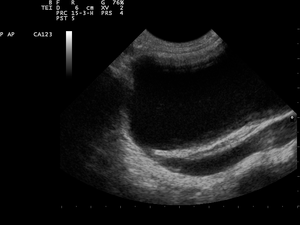

- Abdominal ultrasound

An abdominal ultrasound might suggest the presence of VUR if ureteral dilatation is present; however, in many circumstances of VUR of low to moderate severity, the sonogram may be completely normal, thus providing insufficient utility as a single diagnostic test in the evaluation of children suspected of having VUR, such as those presenting with prenatal hydronephrosis or urinary tract infection (UTI).

VCUG is the method of choice for grading and initial workup, while RNC is preferred for subsequent evaluations as there is less exposure to radiation. A high index of suspicion should be attached to any case where a child presents with a urinary tract infection, and anatomical causes should be excluded. A VCUG and abdominal ultrasound should be performed in these cases